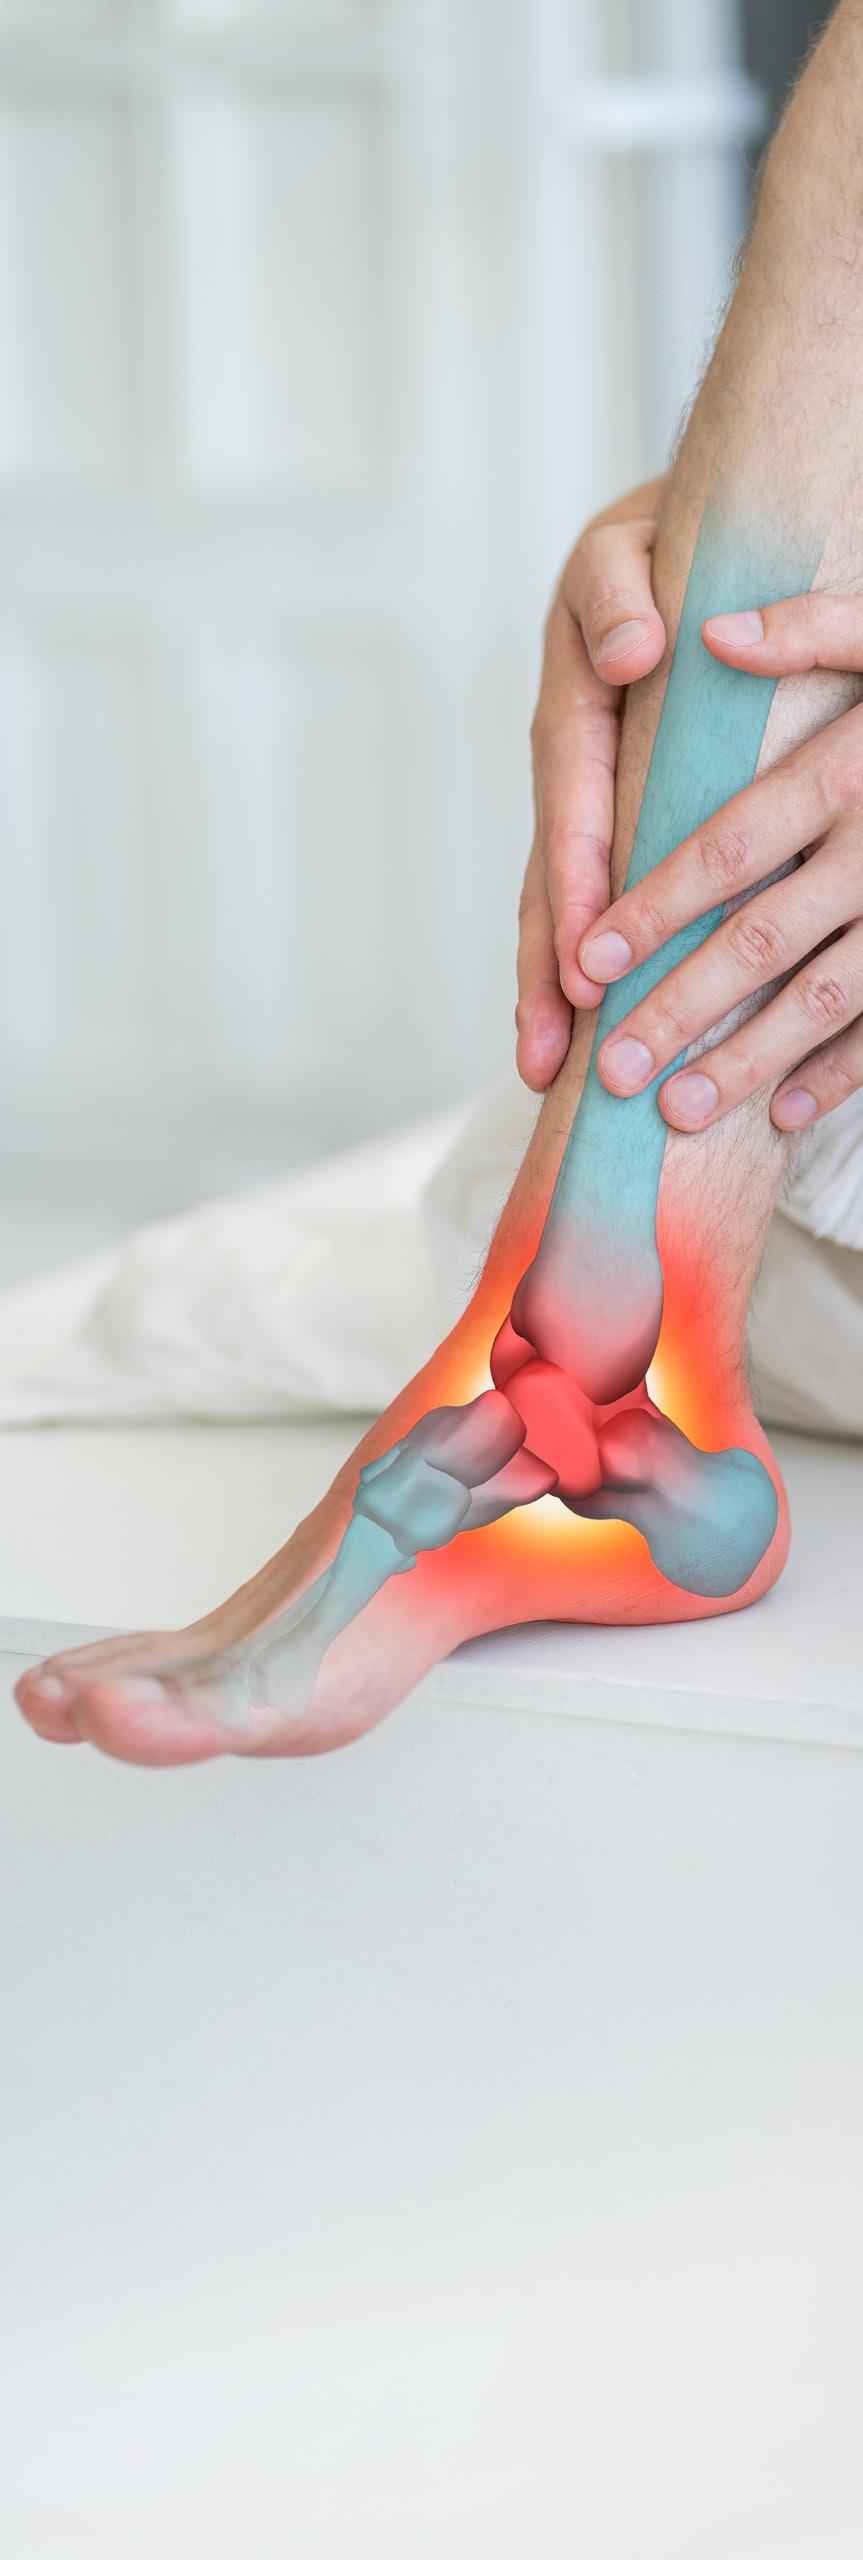

DEIN SPRUNGGELENK

Das Sprunggelenk verbindet die Unterschenkelknochen mit den Fußknochen. Es besteht aus zwei Teilen: dem oberen und dem unteren Sprunggelenk. Das obere Sprunggelenk ermöglicht es, den Fuß nach oben und unten, ein wenig auch zur Seite zu bewegen. Es wird von drei Knochen gebildet: dem Schienbein und dem Wadenbein des Unterschenkels, sowie dem Sprungbein des Fußes. Das untere Sprunggelenk verbindet das Sprungbein mit den Knochen der Fußwurzel und dem Fersenbein. Es ist weniger beweglich als das obere Sprunggelenk und erlaubt ein leichtes seitliches Kippen des Fußes sowie ein Schwenken nach innen und außen. Die Enden der Knochen sind mit Knorpel überzogen. Diese fängt Stöße auf und verringert die Reibung. Sehnen, Bänder und die Gelenkkapsel halten das Gelenk zusammen, stabilisieren und unterstützen seine Beweglichkeit.

Das Sprunggelenk muss starke Belastungen aushalten: Beim Laufen und Springen können Kräfte auftreten, die dem Mehrfachen des Körpergewichts entsprechen. Bei zu starker Belastung können die Bänder aber überdehnt werden oder reißen.

Bänderdehnungen und -risse im Sprunggelenk gehören zu den häufigsten Verletzungen.

Die meisten Ballsportarten erfordern häufiges Springen, schnelle Schrittabfolgen und abruptes Starten und Stoppen.

Bei solchen Bewegungen werden die Sprunggelenke stark beansprucht. Ein falsches Aufkommen oder ein Fehltritt – schon knickt der Knöchel schmerzhaft um. Doch auch im Alltag kann es passieren, dass man mit dem Fuß ungünstig aufkommt oder das Gelenk versehentlich verdreht.

Was kann man tun, wenn das Sprunggelenk weh tut?

Als wichtigste Sofortmaßnahme sollte man das Fußgelenk auf keinen Fall weiter belasten. Am besten kühlt man es mit Kühlpads oder Eis. Kompression durch einen Verband oder eine Bandage

26 das Gesundheitsmagazin

lindert die Schmerzen im Sprunggelenk und verhindert, dass der Knöchel übermäßig anschwillt. Die meisten Verstauchungen ohne Bänderriss sind nach zwei Wochen größtenteils überstanden: Auch wenn der Fuß noch nicht wieder voll belastet werden kann, schmerzt er meist kaum noch. Sind die Bänder angerissen oder gerissen, kann es Wochen dauern, bis das Sprunggelenk keine Probleme mehr macht.